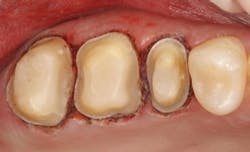

Fig. 4 — Excessive tissue removal with laser after cord placement.

Fig. 5 — Note that the tissue is healthy after placement of restorations and healing, but there are areas of permanent loss of tissue.

Clinicians worldwide have rapidly adopted lasers (primarily diode lasers) due to the decreased cost and the need for digital intraoral imaging. The chairside CAD/CAM community (E4D, CEREC, LAVA C.O.S., etc.) has adopted lasers for more than just the hype and appeal to patients. Proper laser use can result in a very clean and dry field without blood and excess moisture. This is primarily due to the quick hemostatic action of lasers on tissue. When used carefully and at the appropriate setting, lasers can be just as fast if not faster than cord placement. However, improper laser use (primarily by those with inadequate training) can result in tissue height post-healing at a more apical level than desired. It is most likely incorrect to call this condition gingival recession, as the more apically positioned gingival crest is due to blatant misuse or iatrogenic dentistry (Figs. 4 and 5). However, with adequate training, lasers can be an excellent adjunct for tissue management in many dental procedures. Excellent laser options come from Biolase, CAO, Discus/Philips, and Ivoclar.